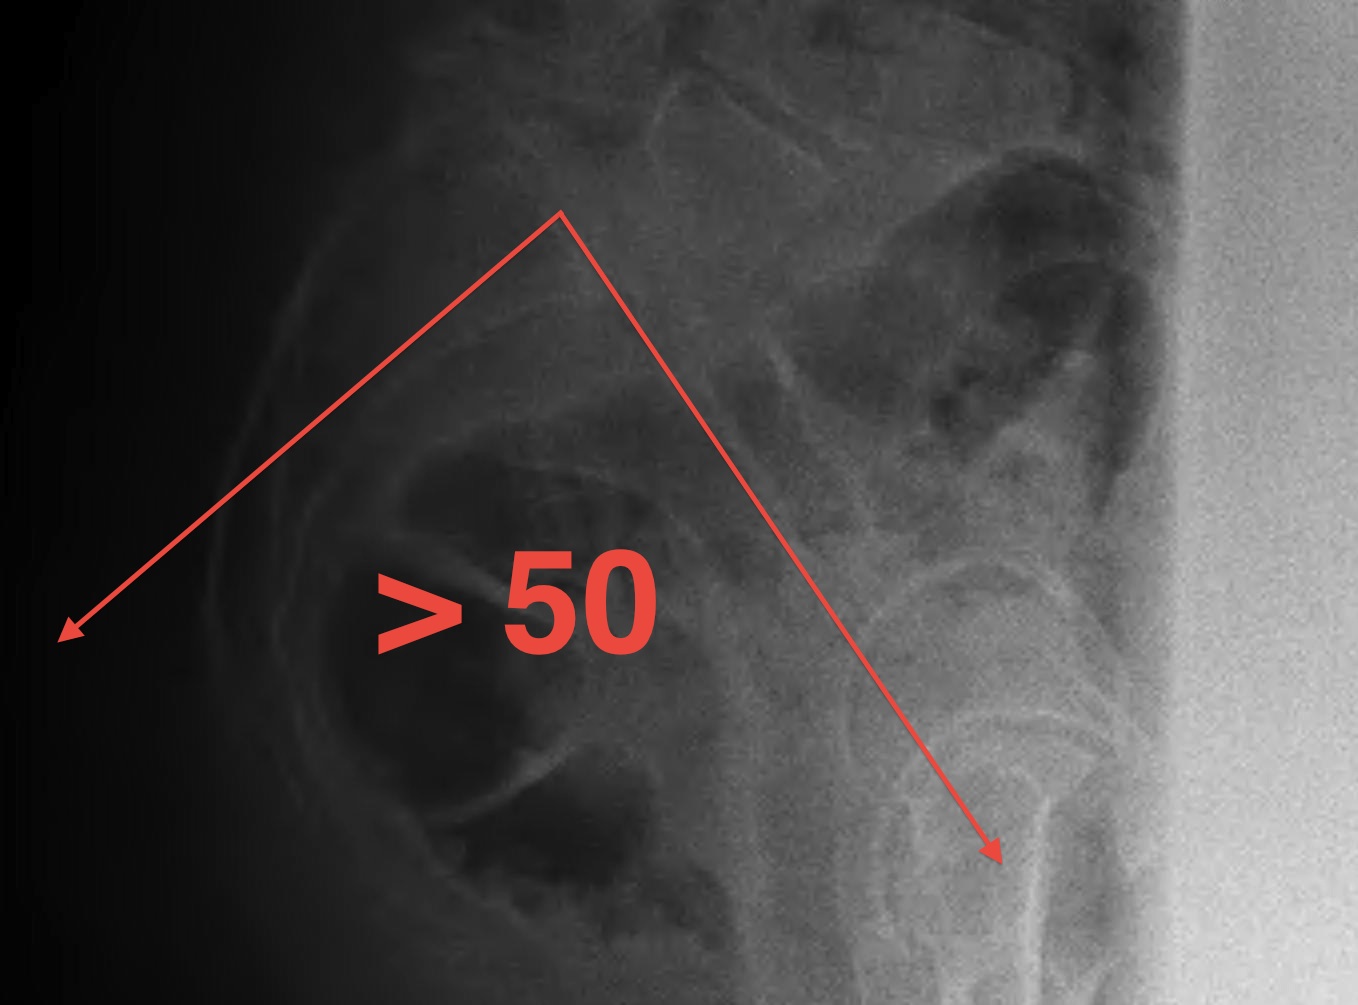

Pelvic Incidence

Isthmic associated with increased pelvic incidence > 50o

- patients have increase lumbar lordosis with increased shear stress

- predisposed to pars fracture if engage in certain sports with hyperextension

Measurement

- line superior border sacrum / sacral slope

- drop perpendicular line from centre of sacral slope line

- line to centre femoral head

- pelvic incidence is line between the two

Stability

- stable / slip < 50%

- unstable / slip > 50%